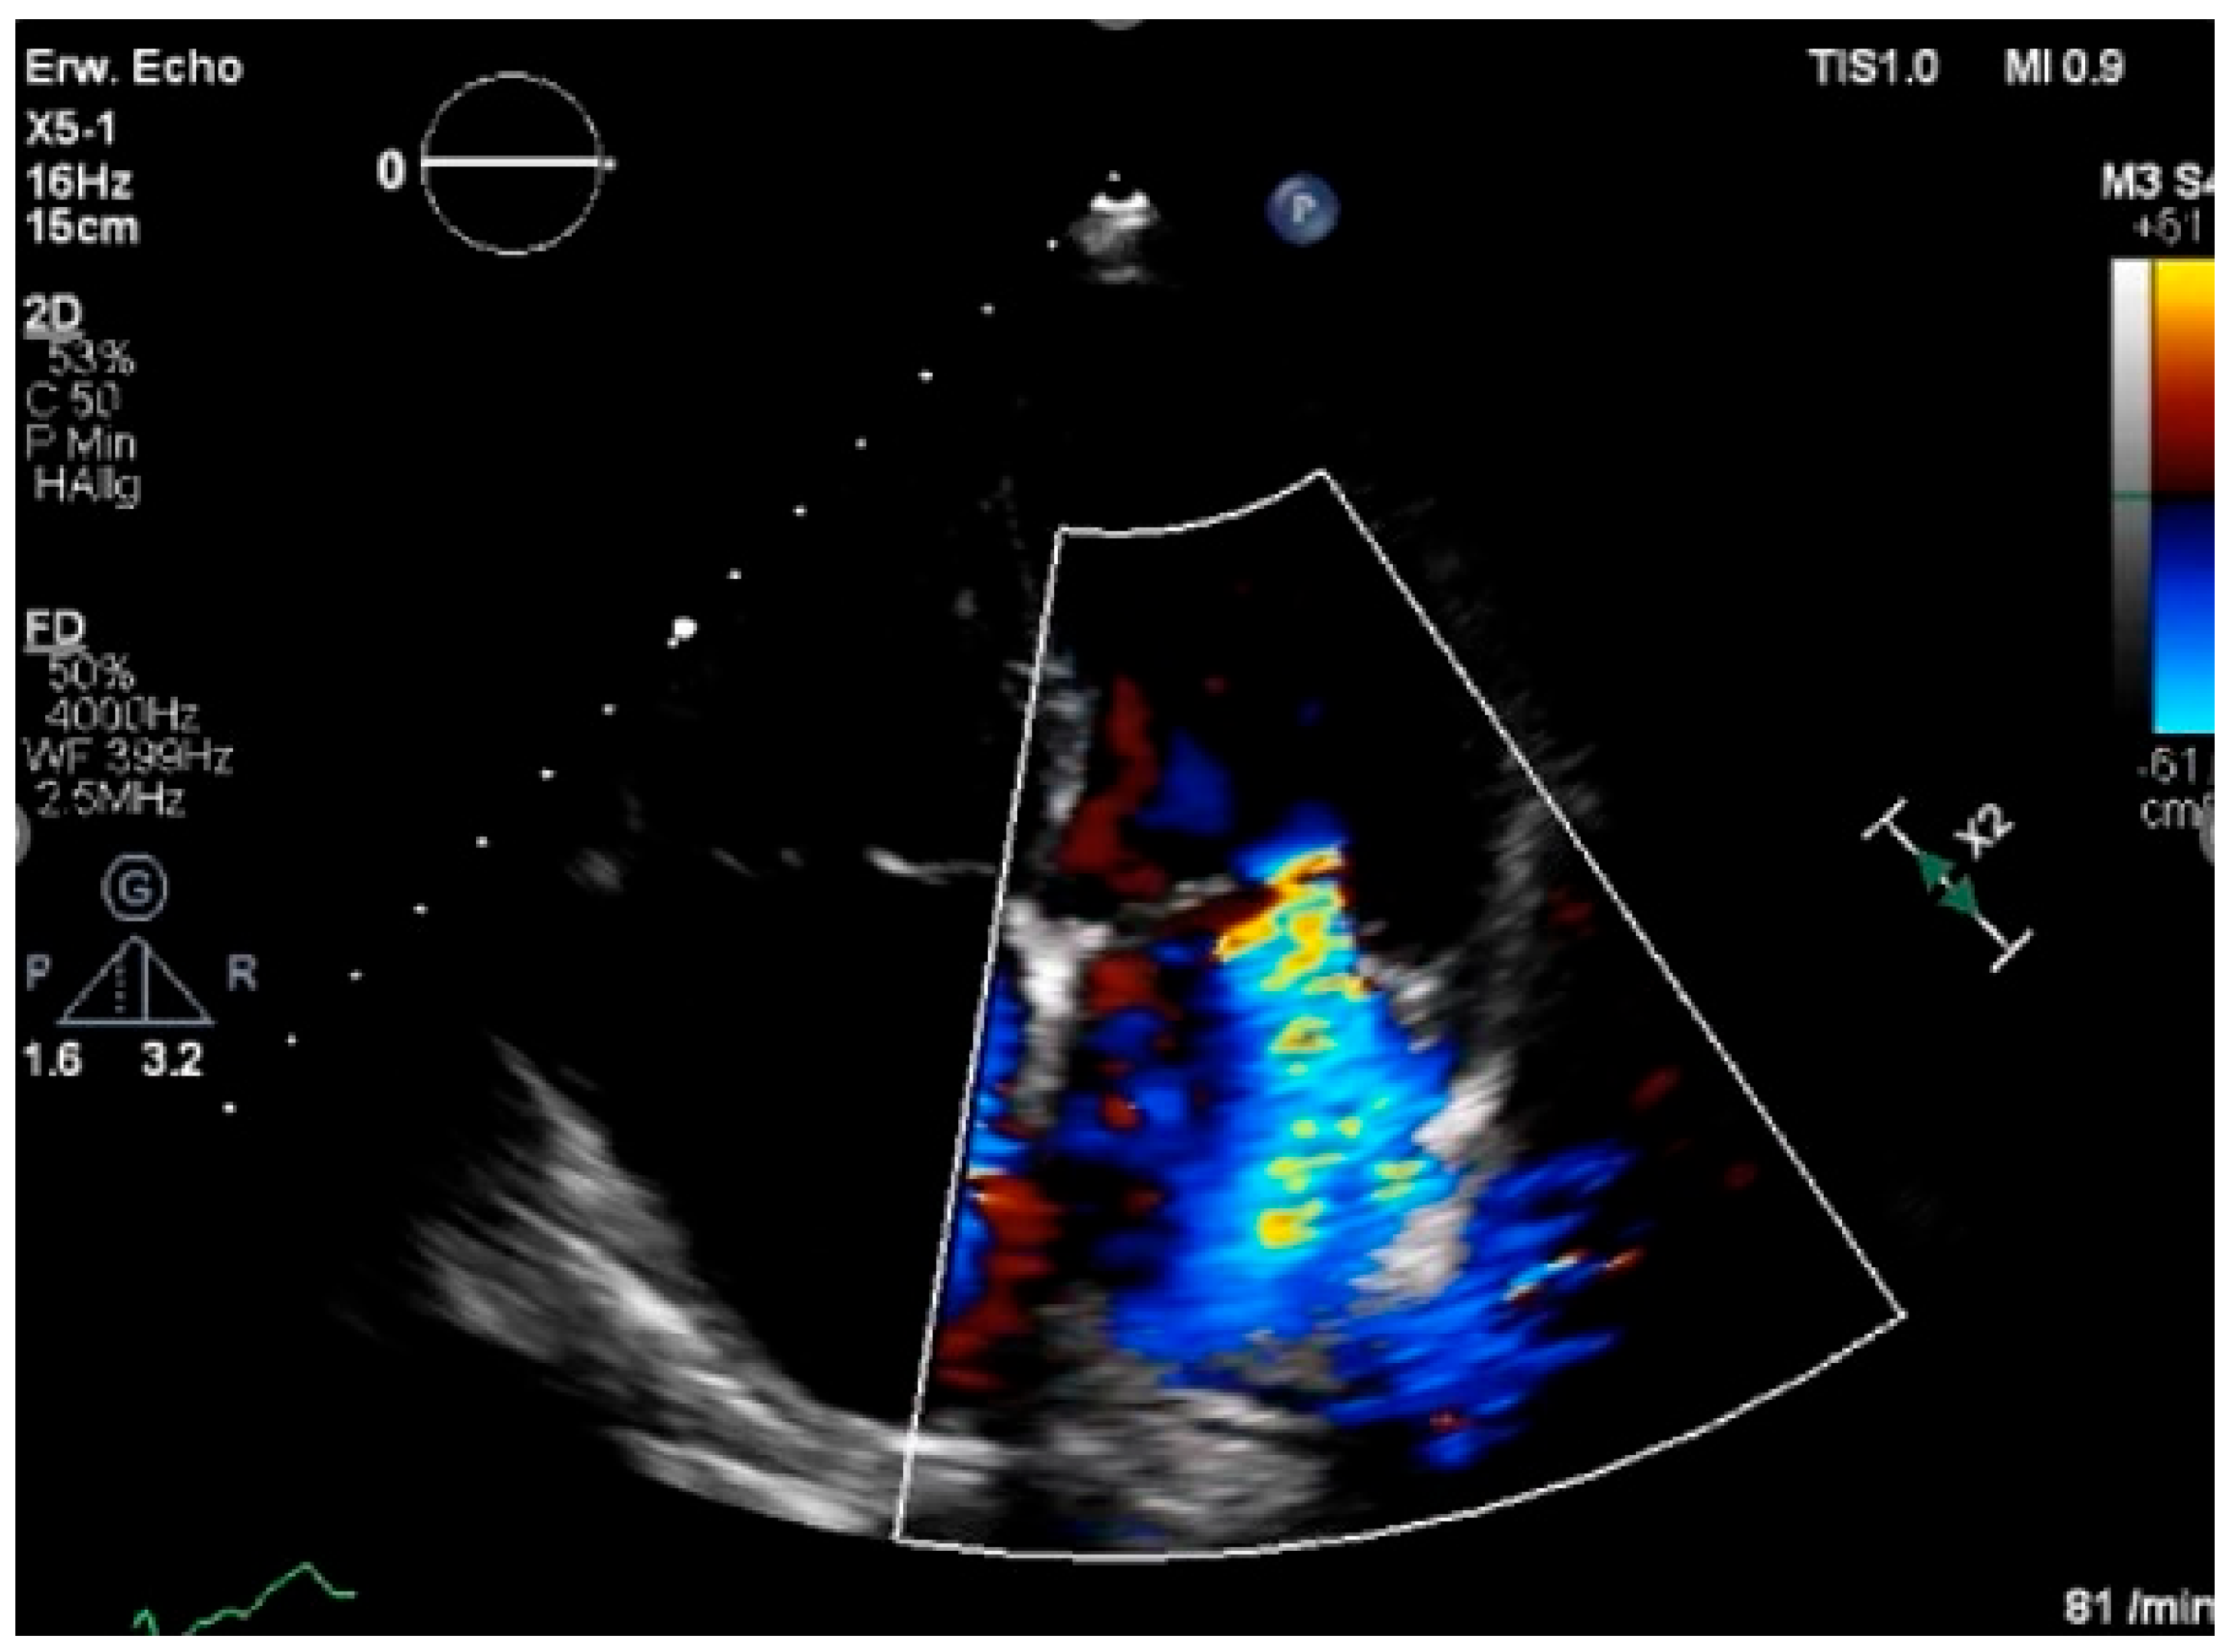

3.1. Echocardiography

3.1.2. Surveillance and Identification of CTRCD

Left Ventricular Systolic Function